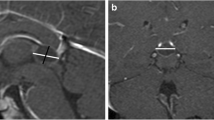

In Fig. 4a, we plotted the linear regression line with 99 % prediction interval of the width (which is similar to the maximum diameter of the gland) of normal solid pineal glands (Table 1) together with the maximum diameter at time of diagnosis of the asymptomatic trilateral retinoblastomas as published in the meta-analysis by De Jong et al. [2] (one circle represents one pineoblastoma case, n = 27; see Fig. 4a). Eighty-nine percent (24 of 27; 95 % CI 71–89 %) of the pineal trilateral retinoblastoma cases, especially of interest, 93 % (13 of 14; 95 % CI 66–100 %) of the solid pineoblastomas, lie beyond the upper bound of normal pineal glands. Most pineoblastomas will not be symptomatic before they reach a certain size; see Fig. 4b where we plotted both the symptomatic (n = 44) and asymptomatic pineoblastomas (n = 27). Figure 4c shows which symptomatic pineoblastomas were solid or (partially) cystic.

Regression line of the normal solid pineal gland width (mm) versus a maximum diameter (mm) of only asymptomatic pineoblastomas, b maximum diameter (mm) of both symptomatic and asymptomatic pineoblastomas, and c maximum diameter (mm) of only symptomatic pineoblastomas. *99 % prediction intervals. †These pineoblastomas are shown in the graph with a size of 10 mm, but had a reported size of 5–15 mm